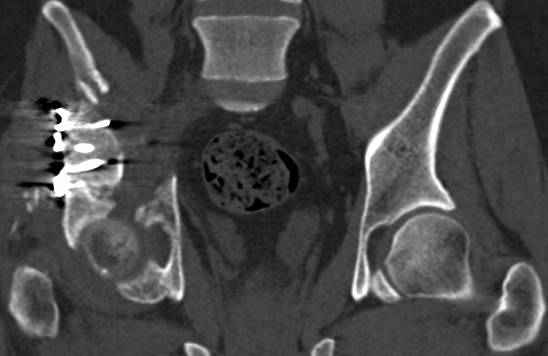

высылаю дополнительно сканы.

итак, второй вариант: высокий двухколонный с вовлечением КПС... Ни одно из основных повреждений не репонировано, кроме задней стенки. Скорее всего попытка реконструкции вертлуги сейчас будет очень травматичной и не очень эфективной, т.е. вероятный риск более значим, чем ожидаемая польза... Лучше подождать, и потом сразу эндопротез

подождать сколько, чего? такая дыра в задней колонне не закроется никогда.

потом эндопротез какой? в такой ситуации приходит на ум Burch-Schneider cage, в 35 лет, дальше что делать?